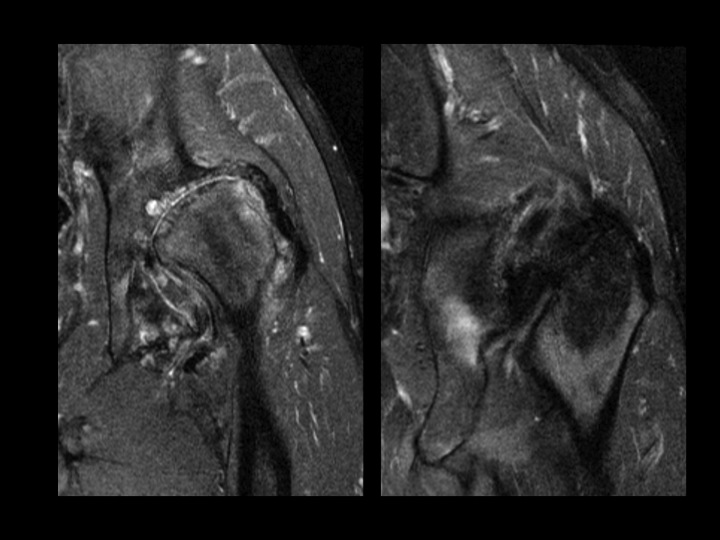

36M with DDH, chronic pain, recent onset more severe pain

I am asking for your thoughts. This is chronic DDH with severe secondary DJD. The femoral head is superiorly migrated with chronic degenerative remodeling of the FH and acetabulum. This brings the posteroinferior acetabular rim and lesser troch into close approximation and appears to cause some sort of impingement. Caudal to that site, there is isolated edema of what is either the Quad Femoris or possibly the Add Magnus (I am confused by the anatomic distortion), which cannot be due to direct muscle friction. I do not know if the Acetabular-Less Troch friction is the direct cause of symptoms, if that is causing nerve impingement, or if there is a muscle strain due to the abnormal stress of the deformity (seems least likely as the deformity is chronic). Please help.

acetabular-femoral impingement